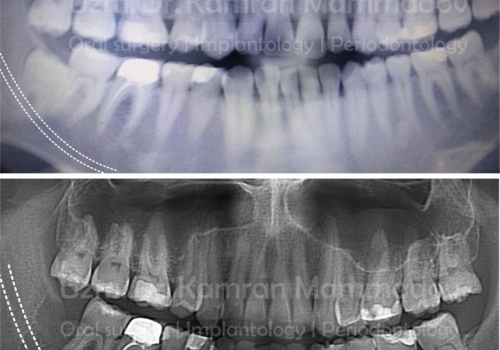

Normal halda insanın diş sırasında hər çənədə iki ədəd olmaqla, ümumilikdə dörd agıl dişi mövcuddur. Ağıl dişinin çıxması bəzi şəxslərdə heç bir kliniki əlamət və ya şikayətə səbəb olmasa da, bir çox hallarda müəyyən kliniki əlamətlərlə öyünü biruzə verir. Bu əlamətlər əsasən çənənin arxa tərəfində təzyiq, çənəni açıb baglama əsnasında agrı və məhdudlaşma kimi özünü göstərə bilir. Bu hallarda mütəxəssis konsultasiyasının önəmi olduqca böyükdür. Belə ki müayinə zamanı cərrah-stomatoloq kliniki və radioloji dəyərləndirmə apararaq dişin dogru pozisiyada yerləşib yerləşmədiyi, dişləmə çıxma ehtimalını, agıl dişinin çənəyə görə ölçüsü və çənə darlıgı kimi durumları dəyərləndirərək tətbiq edilməli olan müalicə taktikasını müəyyən edir.

- Ağıl dişi qonşu dişdə karies, sorulma, parodontal problemlər və s. yaradırsa

- Ağıl dişi qonşu dişin çıxmasına məhdudiyyət yaradırsa və diş sırasında deformasiyalara səbəb olursa